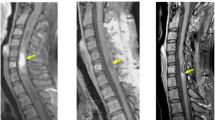

To describe a child with intramedullary glioblastoma at T9–T10–T11, and to discuss the clinical features of this rare pathology.

Spinal cord glioblastoma in children has only rarely been reported. It most frequently involves the thoracic region with a predilection for the second and third decades of life. This report describes one case of thoracic glioblastoma multiforme in a 6-year-old child and reviews other cases reported in the literature.

Laminectomy and excision of the tumour were performed. Postoperative radiotherapy and chemotherapy were given, but 4 months later the patient presented with a brain relapse of the tumour. At 9 months after diagnosis the patient died from cerebral tumour regrowth.

Full neuraxis MRI is always recommended in order to detect possible metastases. The prognosis after multimodality therapy (surgery, radiotherapy, chemotherapy) remains poor. From the literature, only four cases of paediatric patients with long-term survival have been reported.